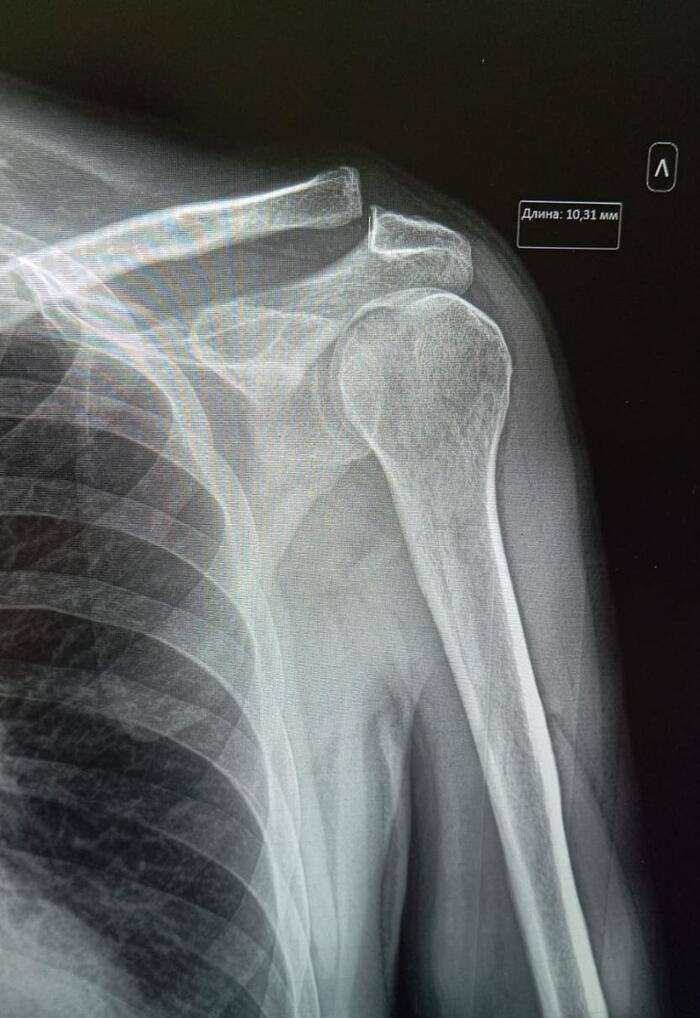

На рентген-снимке видно полное отсутствие плечевого сустава. Взято с wishescards.ru

Смещение акромиального конца левой ключицы на 10 мм выше акромиона.

Заключение: Вывих акромиального конца левой ключицы, вследствие разрыва акромиально-ключичного сочленения.